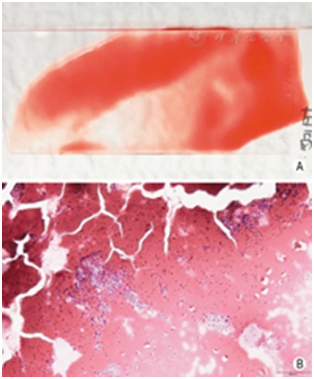

遇标本内血液成分较多时(图26),可以采取以下措施减轻红细胞对镜下观察标本效果的干扰。①将标本分散至数张载玻片,避免单张涂片标本过厚,削弱红细胞对其它细胞的覆盖程度。②穿刺操作时,根据具体情况在抽吸法和非抽吸法之间灵活转换应用。抽吸法穿刺获得标本含血液较多时,可以改为非抽吸法再次穿刺;非抽吸法穿刺获得标本含量较少时,可以改为抽吸法再次穿刺。③采用TCT细胞采集技术,消除红细胞的影响,提高甲状腺结节细胞的观察效果。

图26标本中血液成分过多 A:肉眼观标本量充足,但是以血液为主;B:光镜下见红细胞过多(×10)

专家意见:对于富血供结节,标本中往往难以避免血液成分,应设法减轻红细胞对涂片显微镜下观察的干扰。

当不具备现场快速细胞学评估条件时,通过培训非细胞学医生对置于载玻片上的标本或液基保存液中的标本进行现场裸眼评估的技能,具有较高的可行性和一定的实际效果。现场观察发现标本稠厚,意味着标本中细胞数量更多、更充分,显微镜下的细胞学诊断效能更高(图27)。反之,标本稀薄则提示细胞量可能不足,影响细胞学诊断效能(图28)。标本中颗粒物丰富者,意味着镜下细胞量较多,易获得有效诊断,得到阳性结果的比例也更高(图29);颗粒物较少甚或无颗粒物者则反之。尽管现场裸眼评估不能代替镜下分析,但通过评估可合理调整穿刺针数,增强操作者穿刺成功的信心[31]。

图27标本稠厚,且颗粒物丰富 A:肉眼观标本量充足,肿瘤组织颗粒较多,血液成分较少;B:光镜下见肿瘤细胞多,红细胞较少(×10)

图28标本稀薄,血液成分少且颗粒物亦较少 A:肉眼观标本量不足,质地稀薄;B:光镜下见标本稀薄,细胞少(×10)

图29标本量充足,肿瘤组织颗粒丰富 A:肉眼观颗粒物丰富,血液成分较少;B:光镜下观乳头状癌肿瘤细胞的细胞核明显(×10)

专家意见:充分发挥病理医师或受过专门训练的医护技人员的技术能力,于穿刺现场裸眼观察并初步判断标本中颗粒物是否丰富,以指导当场是否需要继续穿刺取材。但是,不应将标本的裸眼观察结果与其病理性质作等同关联。